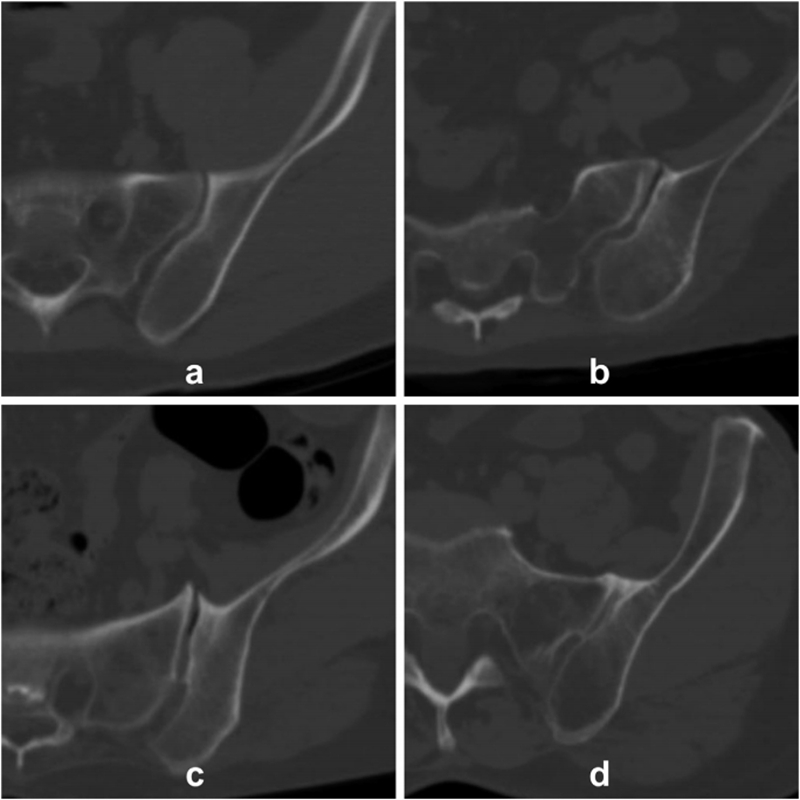

图1 骶髂关节退变程度分类

a:型,无关节退变;b:1型,轻度关节退变;c:2型,重度关节退变;d:3型,骶髂关节融合